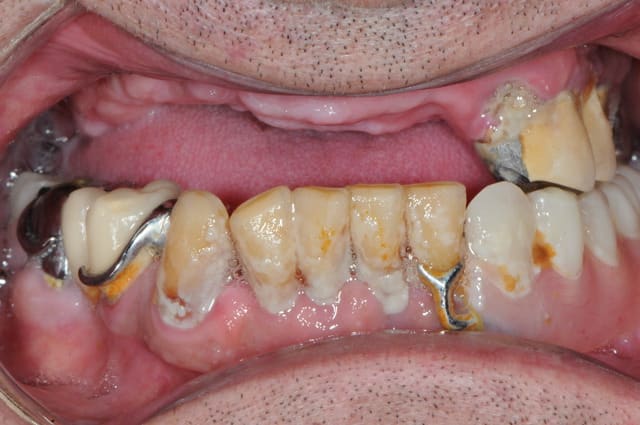

Patient vu en début d'année, parodontite en phase terminale, "monsieur je pense qu'il faudrait vous enlever quelques dents" (voir pano). Lui pas trop pressé apparemment.

Il revient me voir ce mois-ci pour faire sa prothèse. Je lui dit qu'il faut extraire ses dents d'abord.

Il me répond : "ah ben non, elles sont déjà tombées, mais je les garde en bouche ... en attendant!"

Et donc à chaque étape, empreinte, RIM, essayage, je demandais à monsieur d'enlever ses dents, qu'il remettait en place à la fin de la séance.

Du jamais vu pour moi, même si je suis encore jeune dans le métier!!

Fallait que je fasse partager!